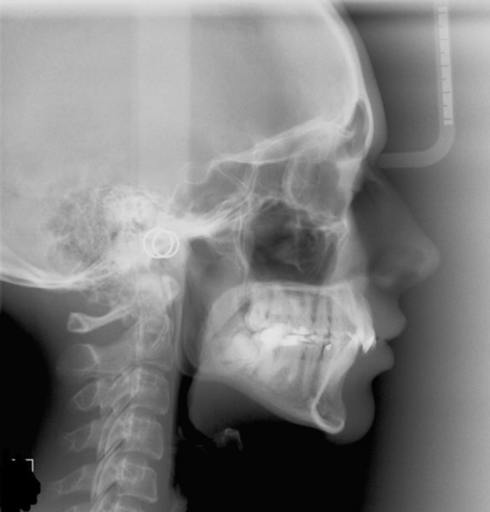

I I'm eighteen years old and i'm from France , and I'm very unhappy by the result of my teeth after braces. I have a narrow smile and a large buccal corridor. Is there a solution like a palatal expander ? One doctor told me that the dna would be the best option for me and another told me that the Alf would be the best option on my case. One doctor told me that the Alf would be the option in my case and another the SARPE SURGERY. Can I send you some pictures ?